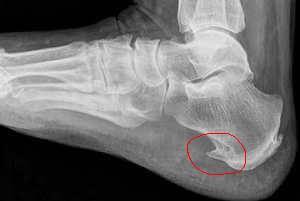

Название патологии выбрано не случайно — на рентгеновских снимках видно костное образование на пятке, напоминающее шпору.

На рентгеновских снимках четко видны изменения в структуре голеностопа, вызванные образованием шпоры, а ультразвуковое исследование выявляет воспалительный процесс в мягких тканях. При пальпации пациент ощущает сильную боль, сравнимую с ходьбой по осколкам стекла.